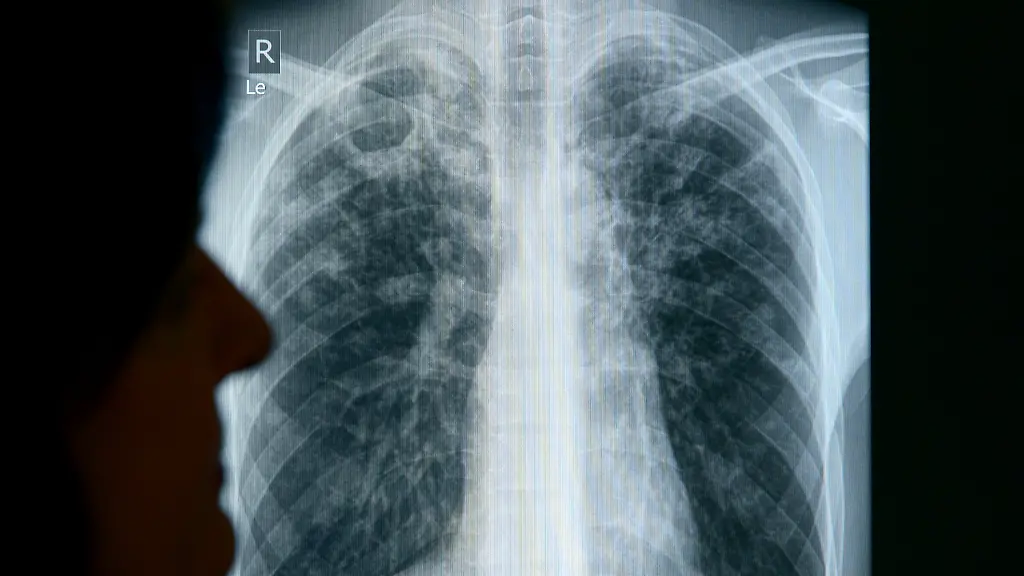

Durch Kürzungen bei HilfsgeldernWHO: Zusammenbruch der Tuberkulose-Programme droht

Unter anderem die USA kürzen ihre Entwicklungshilfe. Auch für den Kampf gegen die Infektionskrankheit Tuberkulose fehlt jetzt Geld. Das könnte dramatische Folgen haben, warnt die WHO. Millionen Menschenleben seien gefährdet - nicht nur in armen Ländern.

Der drastische Einbruch bei Entwicklungshilfegeldern bedroht den Erfolg im Kampf gegen die tödlichste Infektionskrankheit der Welt. An Tuberkulose (TB) sterben nach Angaben der Weltgesundheitsorganisation (WHO) jedes Jahr noch etwa 1,5 Millionen Menschen. 79 Millionen Menschenleben wurden durch frühe Diagnose und Behandlung seit dem Jahr 2000 gerettet - aber ohne weiteres Geld sehe es für die ärmsten Länder düster aus, berichtete die WHO zum Welttuberkulosetag. Durch die weltweite Mobilität ist das eine Gefahr für alle Länder, warnen Gesundheitsexperten. Unter anderem haben die USA Milliarden US-Dollar an verschiedenen Hilfsgeldern eingefroren.